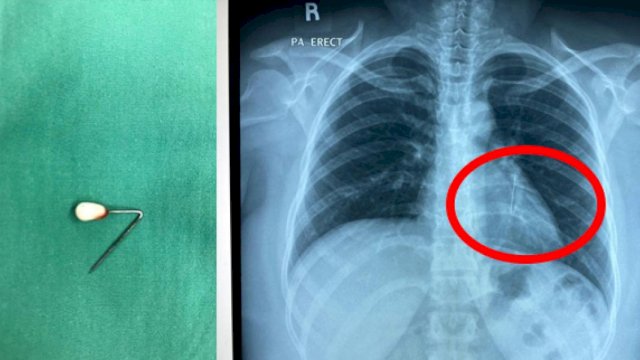

Pedomanrakyat.com, Jakarta – Viral di media sosial momen dokter mengeluarkan jarum pentul dari lambung. Jarum pentul itu disebut tertelan saat pasien hendak memakai hijab.

Operasi tersebut dilakukan oleh spesialis penyakit dalam Prof dr Ari Fahrial Syam, SpPD juga dekan Fakultas Kedokteran Universitas Indonesia (FKUI). Dalam unggahannya, dia menyebut jarum pentul dikeluarkan lewat metode endoskopi.

“Alhamdulullah jarum pentul yang sudah tertanam beberapa hari bisa dikeluarkan dari lambung tanpa operasi. Pelajaran buat yang masih menggunakan jarum pentul buat hijab jangan menggigit jarum saat mau pasang hijab,” tulis dr Ari dalam unggahannya dikutip detikcom atas izin yang bersangkutan, Senin (16/9/2024).

dr Ari merespons dengan mengatakan pasca operasi, kondisi pasien baik dan pulih. Beruntung, jarum pentul yang tertelan tidak memicu perlukaan di area pencernaan.